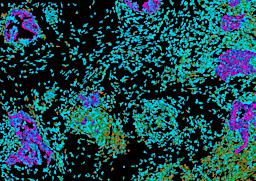

Pancreatic ductal adenocarcinoma is a lethal disease with limited treatment options and poor survival. We studied 83 spatial samples from 31 patients (11 treatment-naïve and 20 treated) using single-cell/nucleus RNA sequencing, bulk-proteogenomics, spatial transcriptomics and cellular imaging. Subpopulations of tumor cells exhibited signatures of proliferation, KRAS signaling, cell stress and epithelial-to-mesenchymal transition. Mapping mutations and copy number events distinguished tumor populations from normal and transitional cells, including acinar-to-ductal metaplasia and pancreatic intraepithelial neoplasia. Pathology-assisted deconvolution of spatial transcriptomic data identified tumor and transitional subpopulations with distinct histological features. We showed coordinated expression of TIGIT in exhausted and regulatory T cells and Nectin in tumor cells. Chemo-resistant samples contain a threefold enrichment of inflammatory cancer-associated fibroblasts that upregulate metallothioneins. Our study reveals a deeper understanding of the intricate substructure of pancreatic ductal adenocarcinoma tumors that could help improve therapy for patients with this disease.